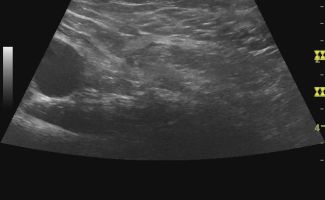

Μέσω του Υπερηχογραφήματος Κοιλιακού Τοιχώματος, ένας εξειδικευμένος Ιατρός-Ακτινολόγος μπορεί να προχωρήσει σε διάγνωση πολλών καταστάσεων που πιθανώς να πλήττουν το κοιλιακό τοίχωμα, όπως:

- Δυναμική Εξέταση: Το Υπερηχογράφημα αποτελεί μία δυναμική μέθοδο απεικόνισης, κάτι που σημαίνει ότι η εξέταση μπορεί να γίνει κατά τη διάρκεια της κίνησης. Αυτή η δυνατότητα είναι ιδιαίτερα χρήσιμη στη μελέτη του κοιλιακού τοιχώματος, καθώς όταν το κοιλιακό τοίχωμα βρίσκεται σε ηρεμία, οι κήλες μπορεί να μην είναι εμφανείς. Με τη δυναμική δοκιμασία Valsalva, είναι δυνατή η διάγνωση μηροκήλης, βουβωνοκήλης ή ομφαλοκήλης.

Το Δυναμικό Υπερηχογράφημα Κοιλιακού Τοιχώματος είναι μία ανώδυνη εξέταση, η οποία δεν απαιτεί προετοιμασία από τον ασθενή. Κατά τη διάρκεια του Υπερηχογραφήματος, η Ιατρός εφαρμόζει ζελέ στην περιοχή και την εξετάζει με την ηχοβόλο κεφαλή.